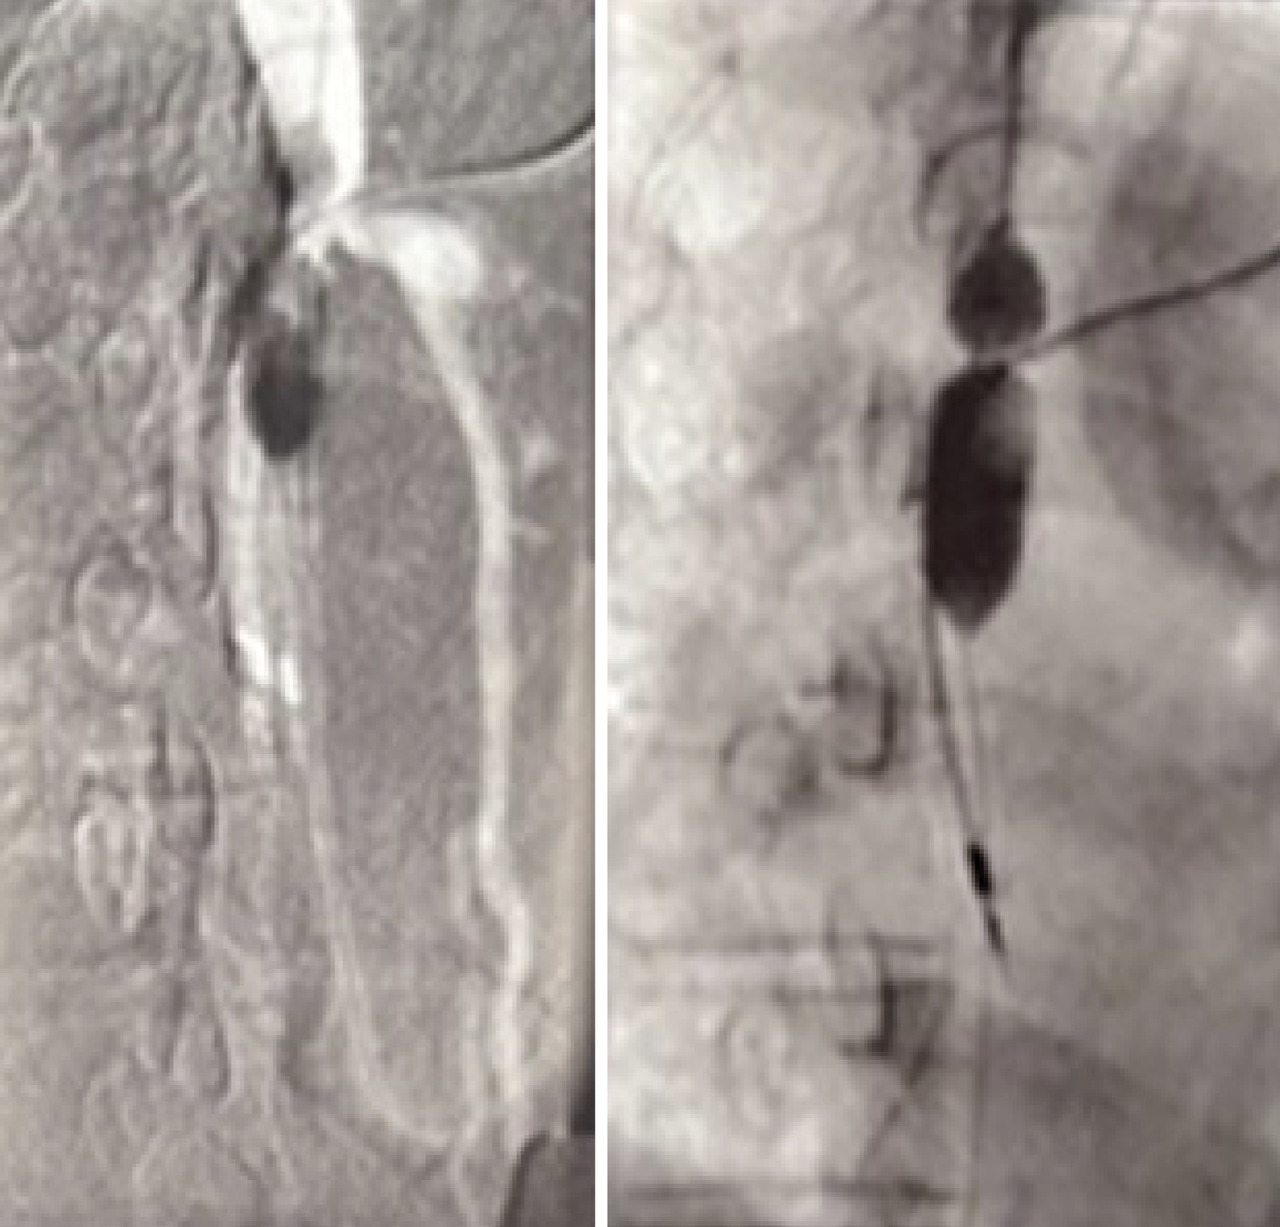

Une consultation de suivi réalisée deux mois plus tard ne révèle aucune complication secondaire (fig. 4).